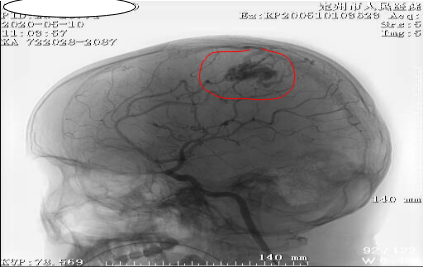

开始,肖主任通过影像发现小雷左顶部动静脉畸形团约3

cm

×1.5cm大小,可见左侧大脑前动脉末端供血,及两根粗大引流静脉引流至上矢状窦。

出血位置顺利找到。